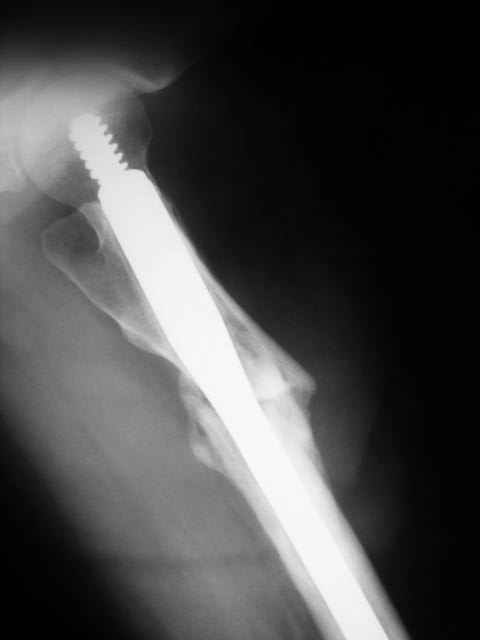

Advice on this case would be appreciated. 59 year old female normal body weight and nonsmoker.

Now 11 months out from initial fixation. No clinical evidence of infection. Closed fracture initially. CT confirms minimal bridging bone. Weightbearing pain in proximal thigh. My initial thought was onlay autogenous bone graft with BMP supplementation and leaving fixation as is. Any benefit to revision fixation and if so what implant? Her ROM and length are symmetric. Thanks.